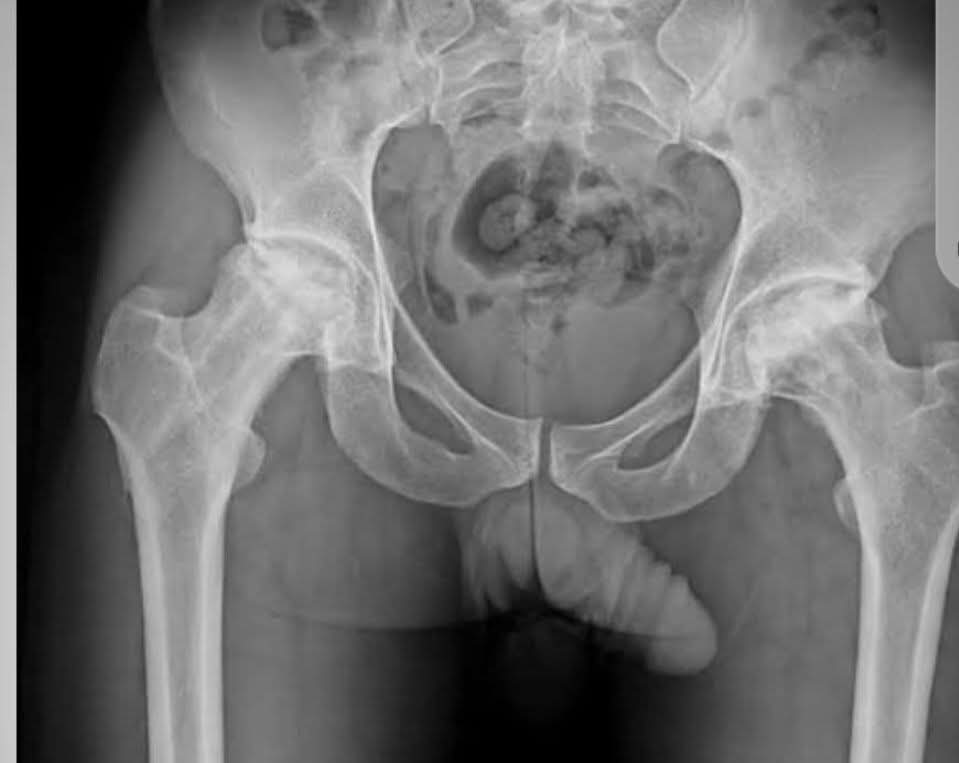

30 years male with bilateral hip pain with a long history of steroid intake. How do i manage? #Orthopedics #xray #health @dr_manish_ydv @Dr_Shiv_kumar_ @DrAkhilX @IhabFathiSulima @DrMedica_13 @drobiy12 @hemo_shk

albertoortegana's tweet image. 30 years male with bilateral hip pain with a long history of steroid intake. How do i manage?

#Orthopedics #xray